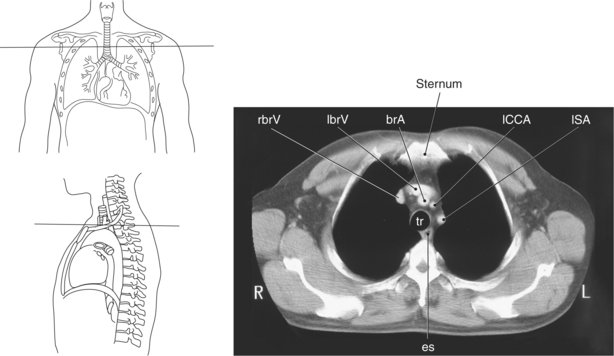

The trachea bifurcates into the left and right mainstem (primary) bronchi at approximately the level of T5. This location is commonly referred to as the carina (Figure 6.9). The right main bronchus is wider, shorter, and more vertical in orientation then the left. At the hilum the mainstem bronchi enter the lung and divide into secondary or lobar bronchi. Secondary bronchi correspond to the lobes of the lungs, thus with three divisions on the right (superior, middle, inferior) and two divisions on the left (superior and inferior) (Figure 6.9, and 6.18 through 6.20). There is further division of the secondary bronchi into tertiary or segmental bronchi that extend into each segment of the lobes (bronchopulmonary segments) (Figure 6.21 and Table 6.1). There are typically 10 segments within each lung. Each bronchopulmonary segment is functionally independent and can be individually removed surgically. The bronchial tree continues to divide many times into smaller bronchi, then into bronchioles (Figure 6.22). Each bronchiole continues to divide until it reaches the terminal end as alveoli, which are the functional units of the respiratory system. Gaseous exchange between alveolar air and capillary blood occurs through the wall of the alveoli.

Throughout its course in the mediastinum, the trachea runs anterior to the esophagus. In cross section, the trachea appears as a round air-filled structure to the point at which it bifurcates at the carina (Figures 6.9 and 6.18). The esophagus appears as an oval-shaped structure that descends through the diaphragm to enter the stomach at the gastroesophageal junction (Figures 6.27 and 6.28).